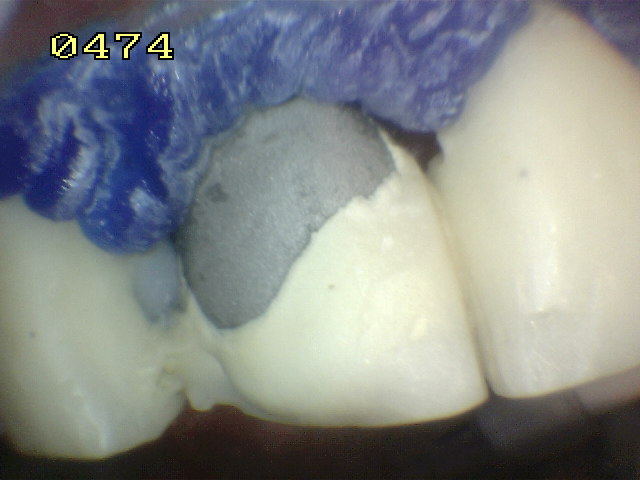

Aislación con barrera gingival

Microarenado con oxido de aluminio de metal y porcelana

Grabado con acido fluídrico por unminuto

Aspecto del grabado del metal y porcelana Se utilizo silano y adhesivo para resina.  Opacificador de metal   y resina microhibrida A3